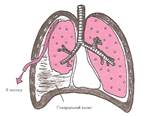

Плевральную полость образуют, как известно, два листка плевры, плотно сращенные с подлежащими тканями: висцеральный листок — с тканью легкого, и париетальный — с внутренней поверхностью грудной стенки (рис. 1). В полости плевры содержится небольшое количество серозной жидкости, которая смачивает поверхность соприкасающихся листков плевры, устраняя тем самым их излишнее трение друг о друга во время дыхания.

Рис. 1. Париетальный и висцеральный листки плевры